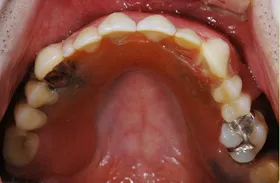

生まれつき歯が生えてこなかったケース

■治療前:生まれつき下顎左右前歯がなく隙間がある

■治療後:矯正治療後、下顎左右3番の2本にインプラント治療

| 主訴 | 生まれつき歯がなく隙間があり、審美障害・咀嚼機能障害がある |

| 治療方法 | インプラント治療 + 矯正治療 |

| 治療期間 | インプラント治療 約6ヶ月 |

| 通院回数等 | インプラント治療 約6回 |

| 費用 | 約94万円(税込) |

| リスク・副作用 | 術後の腫れ・痛み |